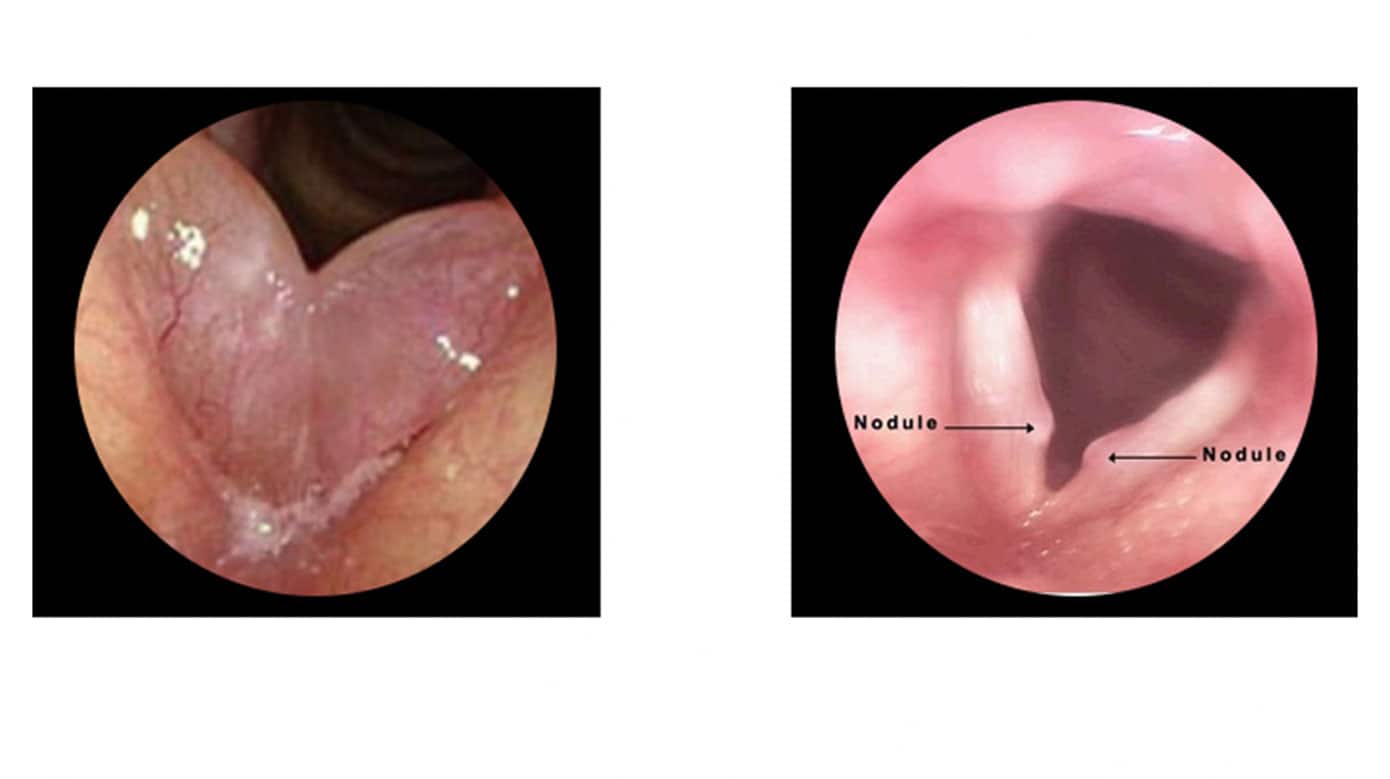

Øre-næse-hals artikler fra Ugeskrift for Læger 20/2025StatusartikelBenigne spytkirteltumorer13. okt. 202512 min.KasuistikIdiopatisk bilateral vestibulopati13. okt. 20255 min.Ugens billedeUspecifikke halssmerter7. jul. 20252 min.KasuistikEksostose ved den indre øregang2. jun. 20254 min.KasuistikKraftig blødning efter biopsi fra nasofaryngealt juvenilt angiofibrom14. jul. 20255 min.StatusartikelNye behandlingsmuligheder for kronisk hoste6. okt. 202513 min.